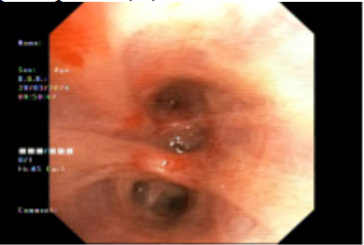

Bệnh nhân được nội soi phế quản phát hiện tổn thương chít hẹp phế quản, được sinh thiết và nhuộm hóa mô miễn dịch kết quả Ung thư biểu mô tuyến nguồn gốc tại phổi. Xét nghiệm gen EGFR phát hiện đột biến xóa đoạn trên exon 19.

Hình 4: Hình ảnh chít hẹp lòng phế quản trên nội soi phế quản.